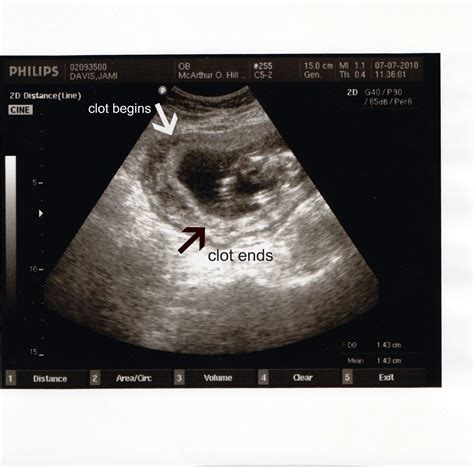

• blood clots after birth pictures